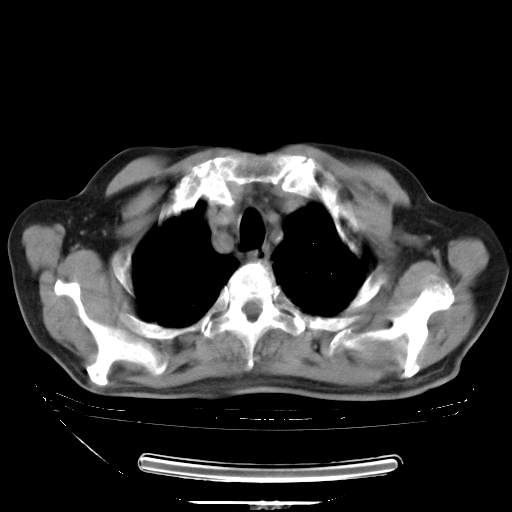

今天复查肺部CT,发现双肺广泛磨玻璃样改变。所以我把3月19日和5月9日相隔50天的肺部CT上传。请大家会诊。

5月9日肺部CT(在4月27日齐鲁医院肺部CT描述部分肺组织磨玻璃样改变,12天后肺组织广泛磨玻璃样改变)

大致读了系列胸部CT:纵隔窗无明显异常,肺窗:从4、27至今:主要是双肺中下野外带可见毛玻璃样改变,目前处于急性肺泡炎阶段,至于原因考虑1、结替组织或胶原血管性疾病所致?2、恶性疾病如恶组在肺部所致的表现或细支气管肺泡癌?3、药物或其它原因如肺蛋白沉着症所致肺泡炎目前不太可能?总之,明天就去请我院的呼吸科、感染科、血液科和临免专家会诊哈。